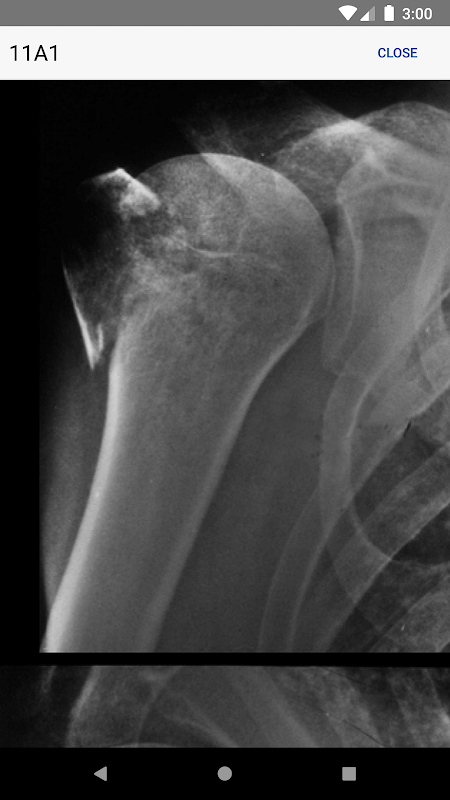

• Informações sobre exames radiológicos utilizados para a classificação de uma fratura específica

• Armadilhas comuns com imagens são abordados

• Todas as novas ilustrações de fratura

• de alta qualidade, raios-x alargáveis estão incluídas